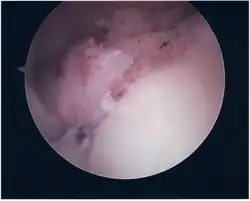

Twelve varieties of SLAP lesion have been described, with initial diagnosis by MRI or arthrography and confirmation by direct arthroscopy.[9]

Surgical treatment of SLAP tears has become more common in recent years. The success rate for repairing isolated SLAP tears is reported between 74-94%.[10] While surgery can be performed as a traditional open procedure, an arthroscopic technique[11] is currently favored being less intrusive with low chance of iatrogenic infection.[12]